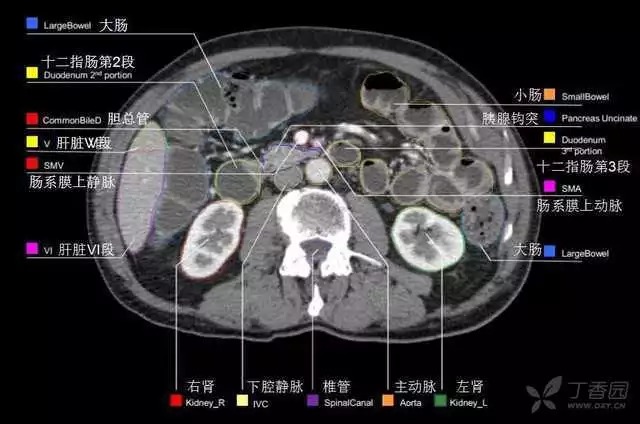

腹部肝脏高清CT断层的图谱

全腹部高清CT图谱,淋巴结彩色图谱,血管解剖图谱大汇总!

肝段,肝内管道的分布规律

美国放射学会ACR官网,对肝脏的区域和节段解剖学概述